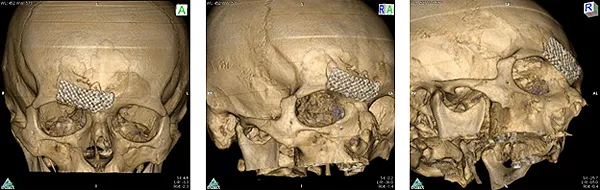

Open reposition of the anterior wall of the frontal sinus, osteosynthesis of the anterior wall of the frontal sinus with a titanium shield

Spiral computed tomography before surgery:

Spiral computed tomography after surgery: